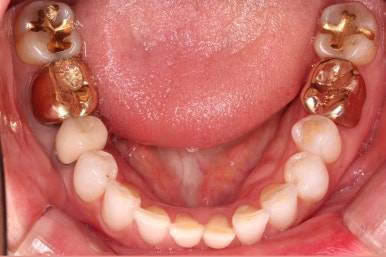

초진 시 입안의 모습입니다.

환자분이 원하셨던 부분은 윗니 작은 앞니가 하나 튀어나와서 개선하고 싶어하셨습니다.

부가적으로 아랫니 앞니가 마모가 심하여 높낮이가 달라보이는 점이었는데요.